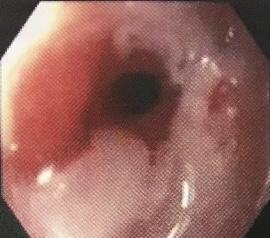

Rétrécissement de l'œsophage

డా. గన్నవరపు నరసింహమూర్తి, CC0, via Wikimedia Commons